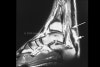

MRI : 아킬레스건 파열(Achilles Tendon Complete tear)

파열된 끝이 말린(retraction) 대걸레 끝의 모양과 유사합니다.